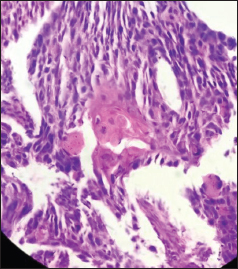

| Figure 4 Lymph node showing metastatic tumor with cells arranged in sheets, nests, and trabeculae in desmoplastic stroma (H and E, ×40)